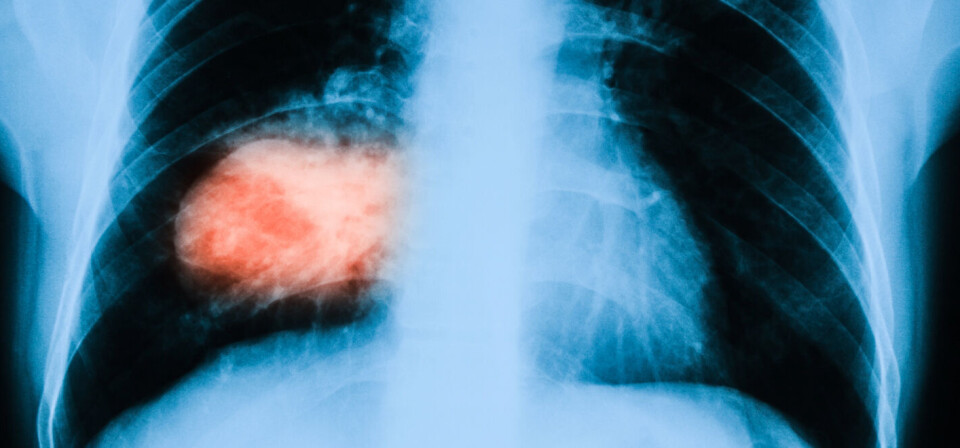

To fase 3-studier, som prøver ut det målrettede kreftlegemiddelet veliparib i kombinasjon med cellegift mot henholdsvis ikke-småcellet lungekreft og trippel-negativ brystkreft, møtte ikke sine primærendepunkter. Det melder AbbVie i en kunngjøring.

Studien på lungekreft omfattet 970 pasienter, og hadde som primærendepunkt totaloverlevelse blant røykere. I brystkreftstudien deltok 312 pasienter, og studien tok for seg komplett respons som primærendepunkt.